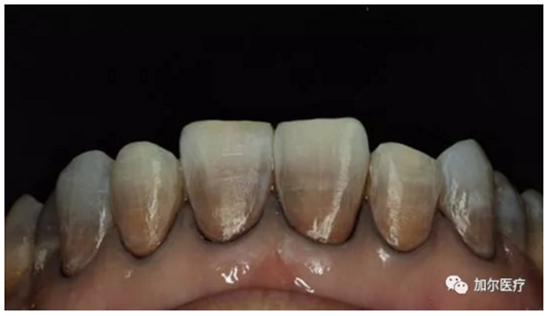

判斷牙齒是否還有知覺(jué)!

1、牙髓病死最大的感知就是牙齒沒(méi)有什么感覺(jué),連吃飯冷熱酸甜一點(diǎn)反應(yīng)都沒(méi)有,另外還會(huì)經(jīng)常出血,一般深齲傷及牙髓剛開(kāi)始是慢性牙髓炎。

2、到后來(lái)牙齒沒(méi)有了營(yíng)養(yǎng)來(lái)源,咬過(guò)硬東西時(shí)牙冠一不小心就會(huì)崩壞。